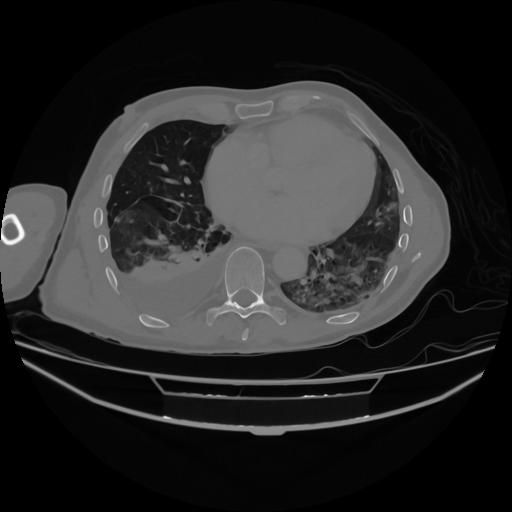

5 CUERPO,CE,Vol,1.0,CUERPO,,